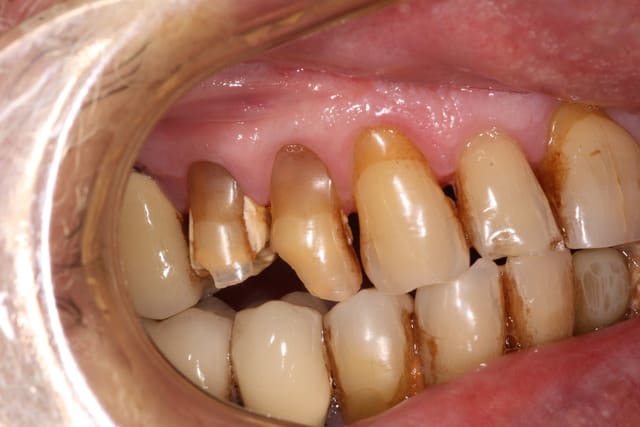

Hello les pros de l'endo,

sur ces 14 et 15 asymptomatiques j'aimerais faire des couronnes sans devitaliser étant donné les grandes chances à mon avis de retrouver un quelconque canal, sur ce patient j'ai eu le probleme sur la 23 que j'ai fini par extraire

comment trouver de la rétention une fois les prepas faites ?

L'avenir de la 14 m'a l'air bien compromis (dent plutôt courte, état parodontal, délabrement important et profond, pas d'endo possible donc pas d'ancrage radiculaire...).

Bon, s'il faut vraiment conserver et couronner la 15 :

- vu que l'endo n'est pas possible (pas possible de trouver un quelconque canal même avec du verifix, et une lime 6/100éme)

- vu que celle-ci est complètement asymptomatique (pas de douleur à la percussion axiale, pas de sensibilité au froid, ni au chaud, pas de lésion apicale visible à la Rx)

=> je ferais une reconstruction avec du compo, collé de manière rigoureuse et avec des tenons dentinaires (à l'ancienne) pour accroitre la rétention...

Puis une taille prériphérique sous le niveau du composite pour obtenir un effet de cerclage et accroite la rétention de la couronne...

Je passerais toute fois par deux mois de couronne prov., histoire de m'assurer qu'aucun symptôme n'apparait.

Mais j'expliquerais bien au patient que ce n'est pas la meilleur solution, et que ça ne sera peut être pas durable dans le temps...

Au vu de la pano, de l'état paro, et des nombreux bricolages qu'a déjà subit ce patient, j'envisagerais une solution plus globale et avec un meilleur pronostic dans la durée.